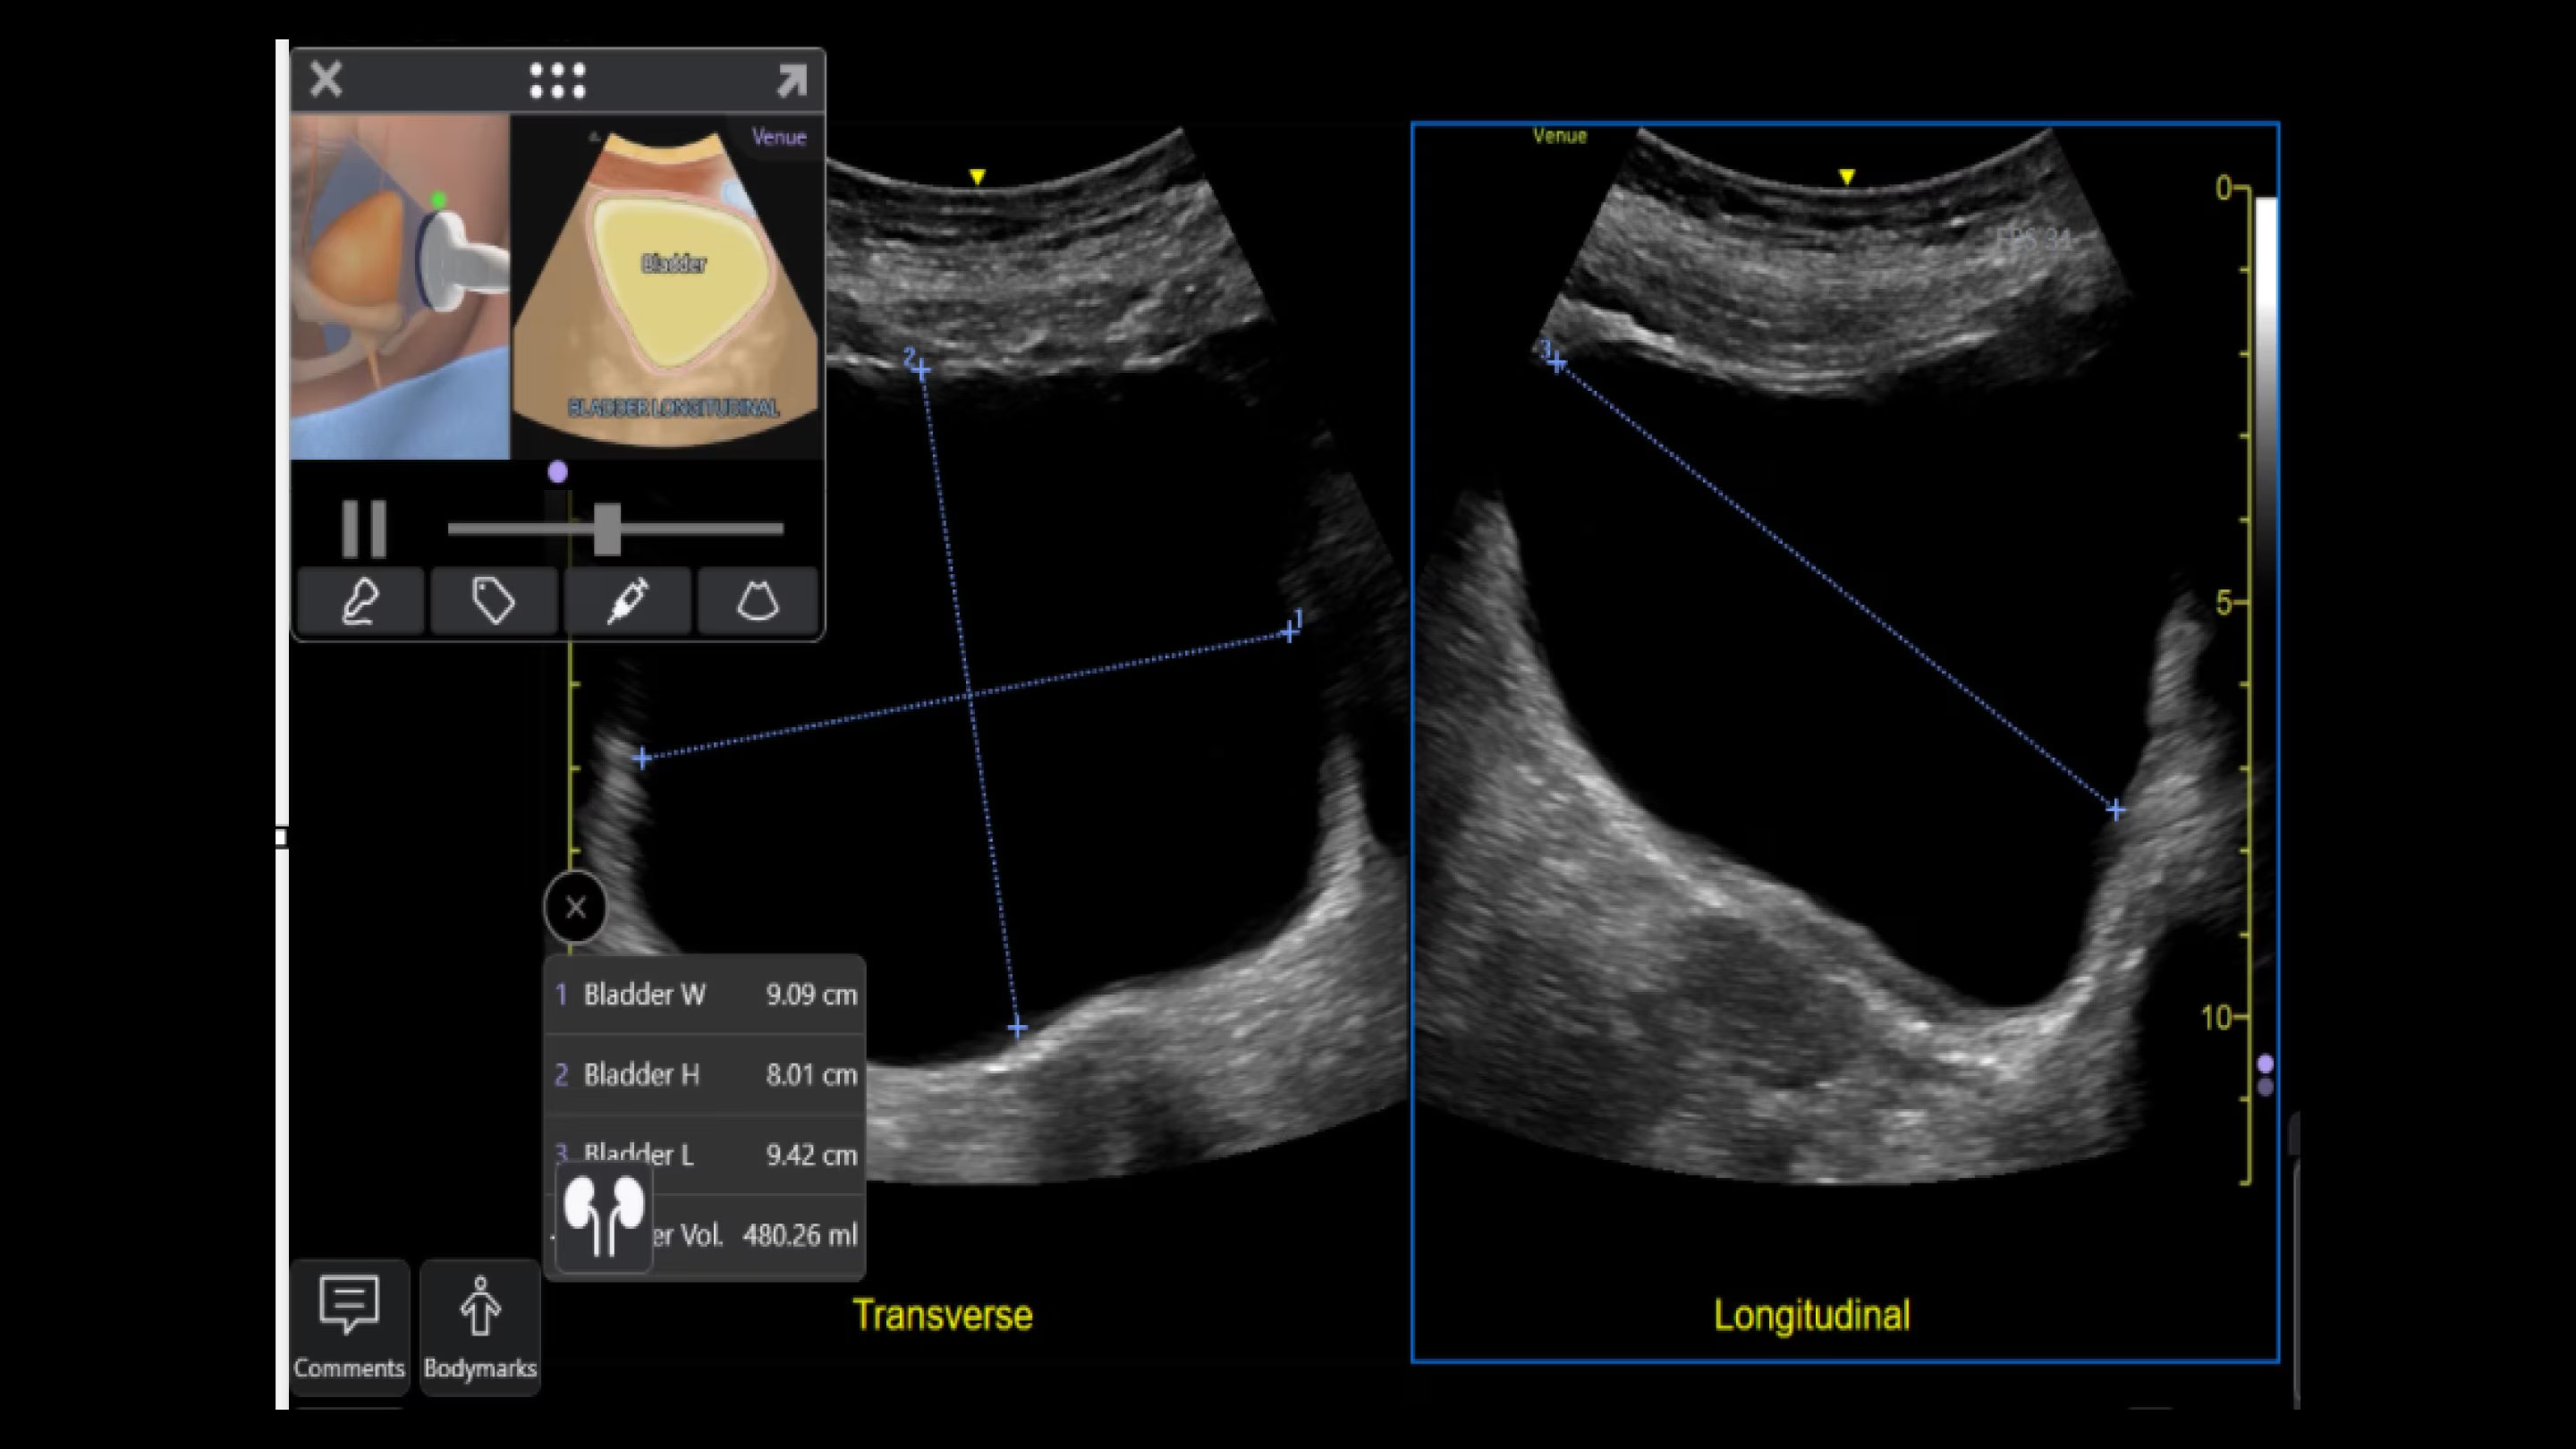

Automated tools

Simplify your workflow with AI-enabled clinical tools.

Helping drive consistency from user to user (whether one is an ultrasound novice or expert), Venue Fit features AI-enabled resources that help clinicians work smarter and more efficiently. Utilizing proprietary algorithms, we synthesize data from numerous patients to ensure accurate calculations for clinical confidence.